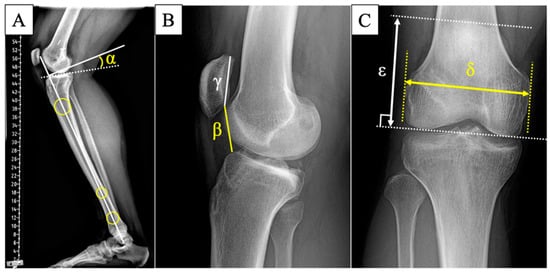

2.4. Radiographic Measurements and Clinical Outcomes